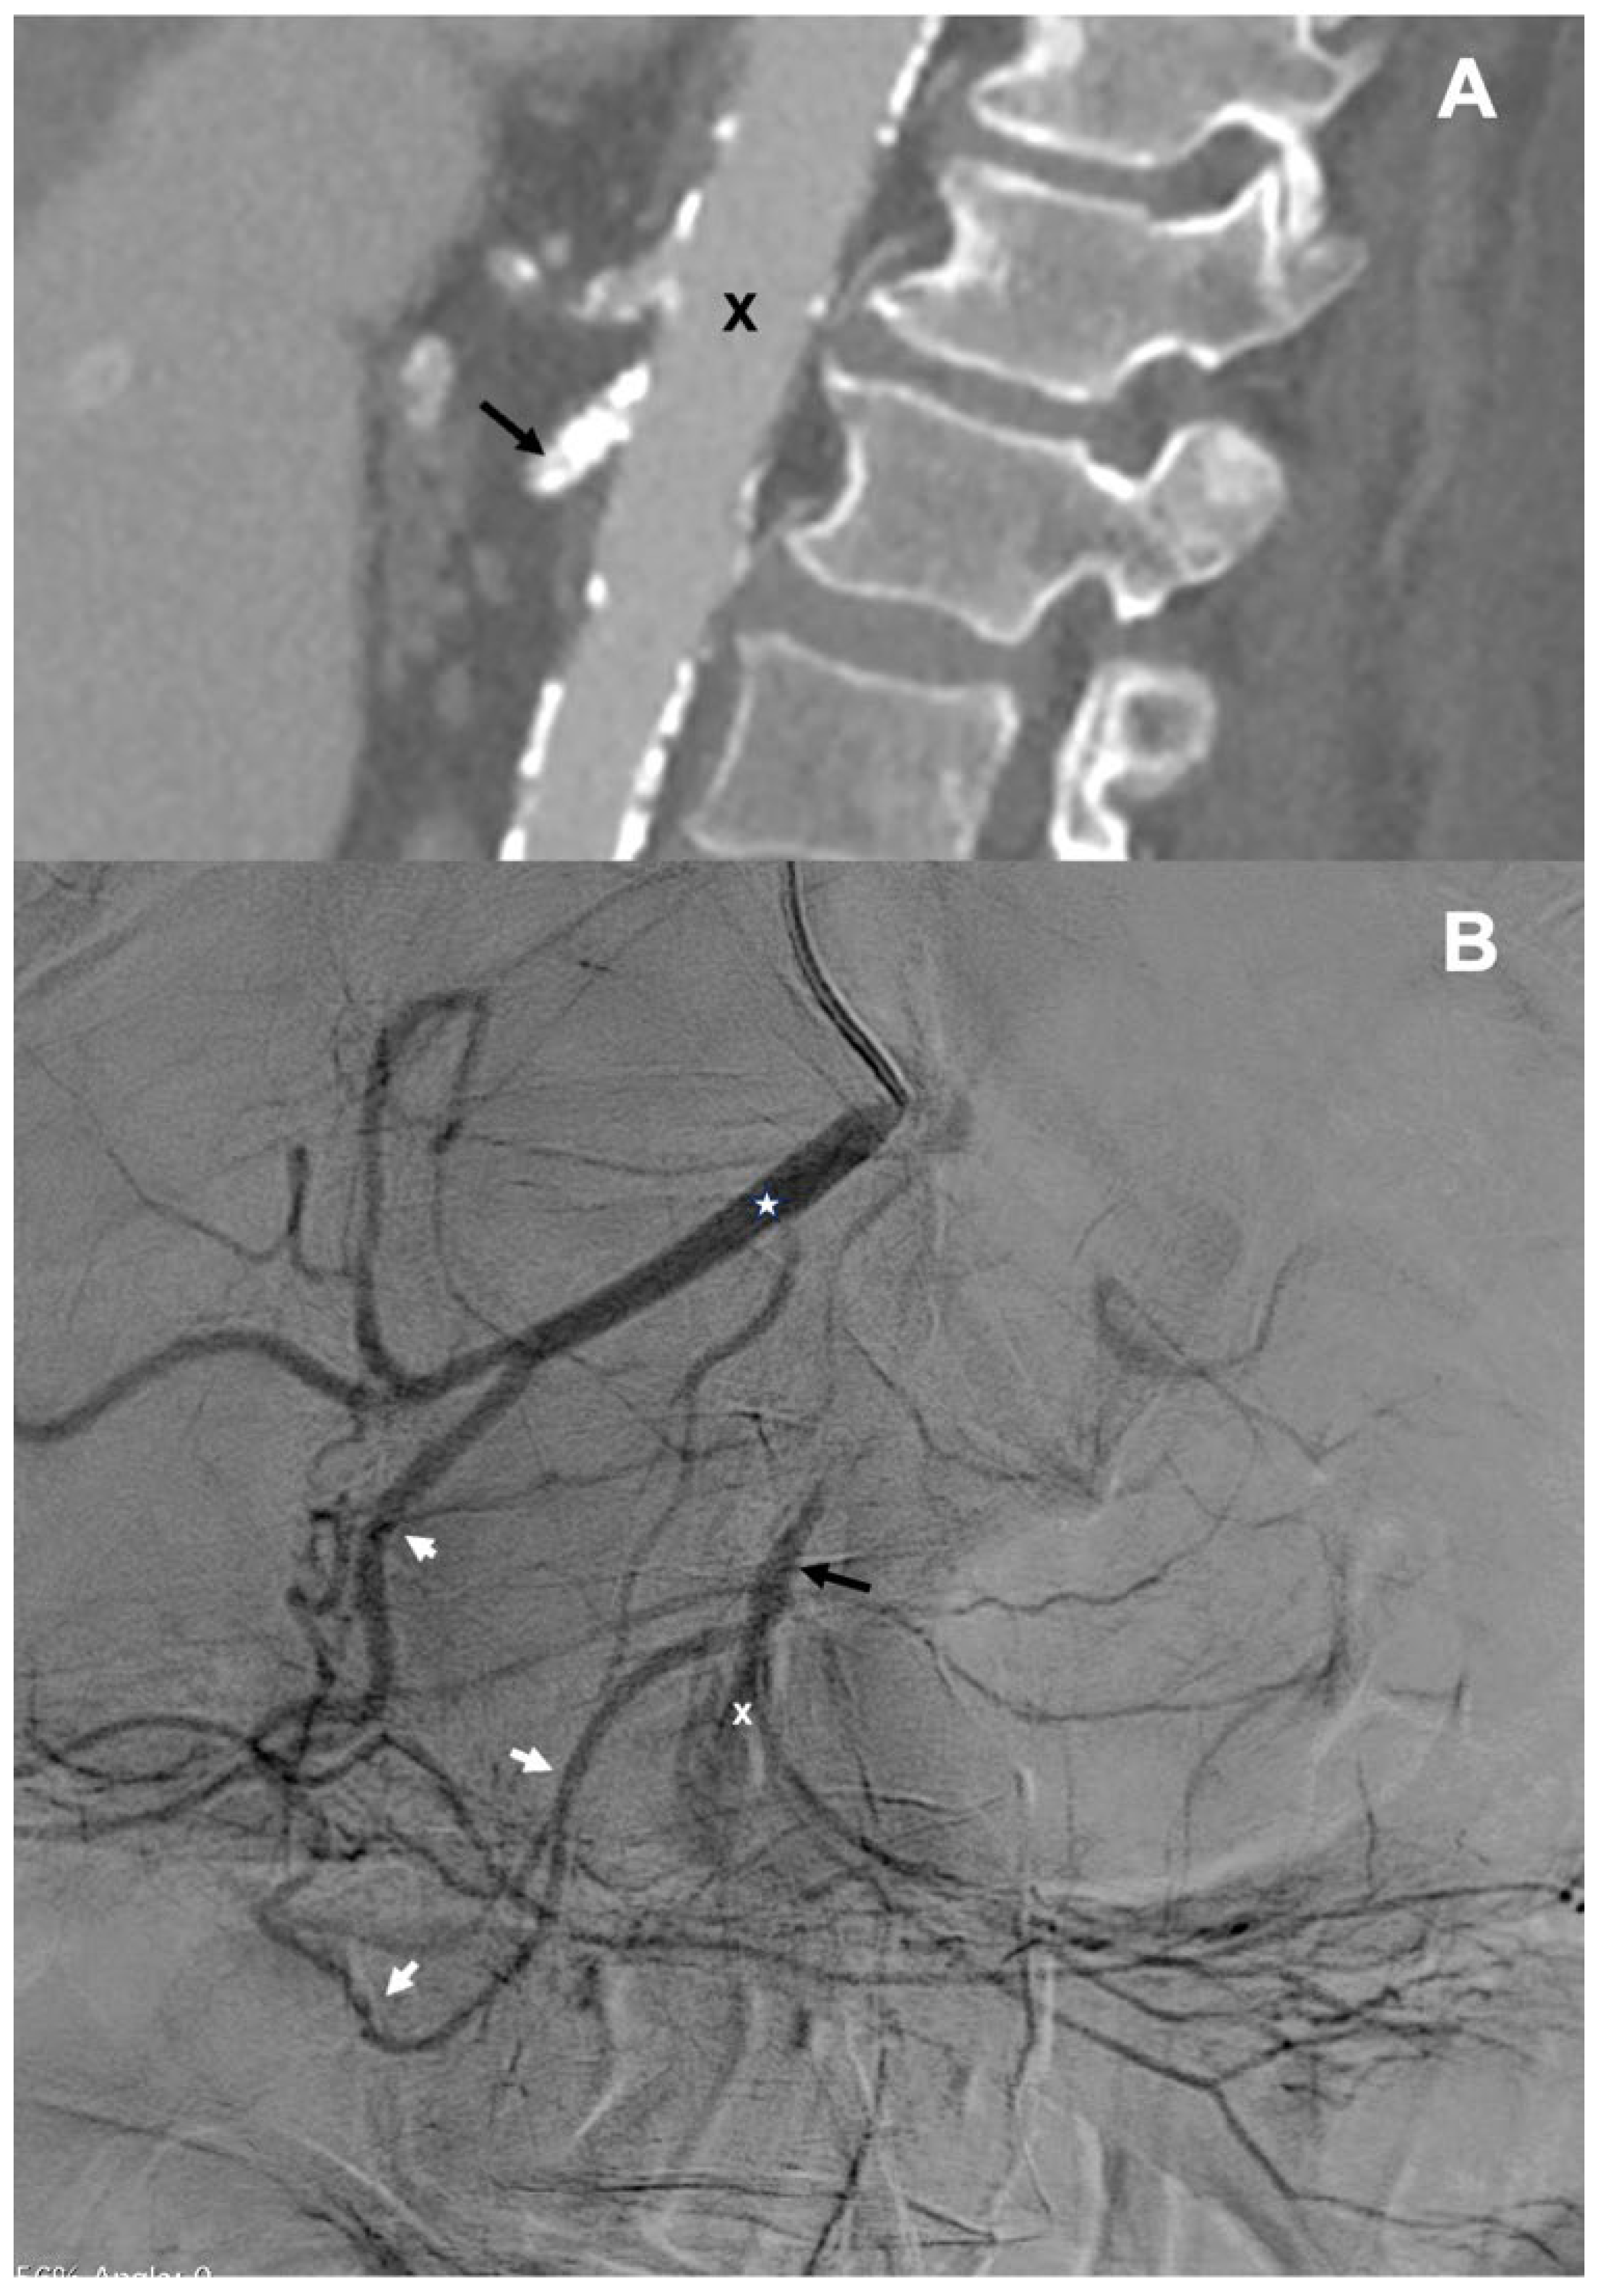

CT angiography, which was performed to diagnose the cause of acute abdominal symptoms suggesting intestinal ischemia, revealed calcified plaques in the SMA, located 3 mm distally from the aorta (Figure 1A). This lesion completely occluded the proximal part of the SMA. This examination also demonstrated a patent celiac trunk, wide common hepatic artery (CHA), and patent, although narrow, gastroduodenal artery (GDA). Distal branches of the SMA were not visible. The overall clinical picture suggested thrombosis of the SMA, resulting in bowel ischemia. Probably, this total occlusion of the SMA resulted from thrombosis of the critical atherosclerotic stenosis at the proximal part of SMA in the settings of heart failure and blood hypercoagulability that could not be properly managed pharmacologically because of recent gastrointestinal bleeding.

Figure 1.

(A)—CT angiography of the aorta (X) and visceral arteries (sagittal projection): a highly calcified plaque 3 mm from the aorta, occluding proximal segment of the superior mesenteric artery (black arrow); (B)—Catheter angiography of the celiac trunk—common hepatic artery (asterisk) and gastroduodenal artery (white arrows) and retrograde inflow to the proximally occluded superior mesenteric artery (black arrow) and no inflow to the distal part of superior mesenteric artery (X).

Catheter angiography of the abdominal visceral arteries, which was performed from the left brachial access, did not show the SMA. When the catheter was advanced to the CHA, the proximal part of the SMA was revealed. This artery received inflow through the GDA. Also, several proximal jejunal branches were shown, while other branches of the SMA were not visible (Figure 1B). Considering the fact that the origin of SMA was not visible, we decided to recanalize this artery in a retrograde manner via the branches of the celiac trunk.